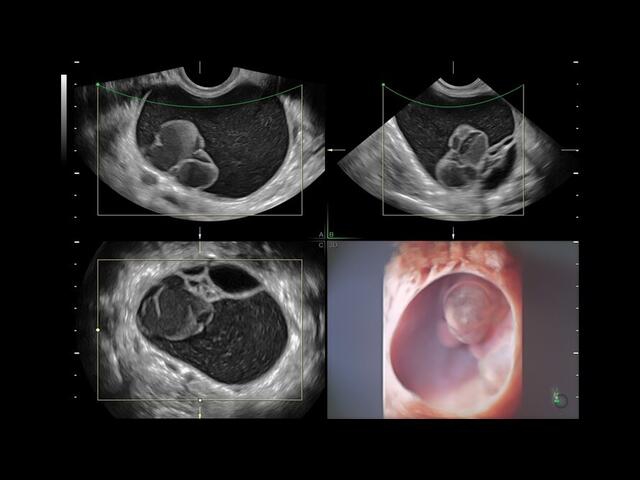

• Технология контрастной 3D-визуализации VCI для повышения качества изображений в одной и трех проекциях.

• Режим ультразвуковой томографии TUI для одновременного просмотра нескольких параллельных срезов в режиме реального времени и кинопетли.